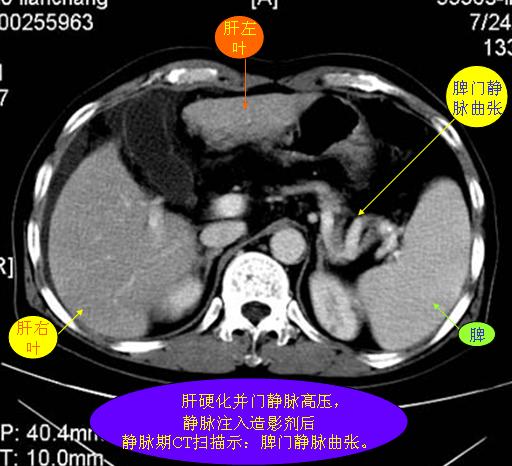

腹部ct解剖与基本病变